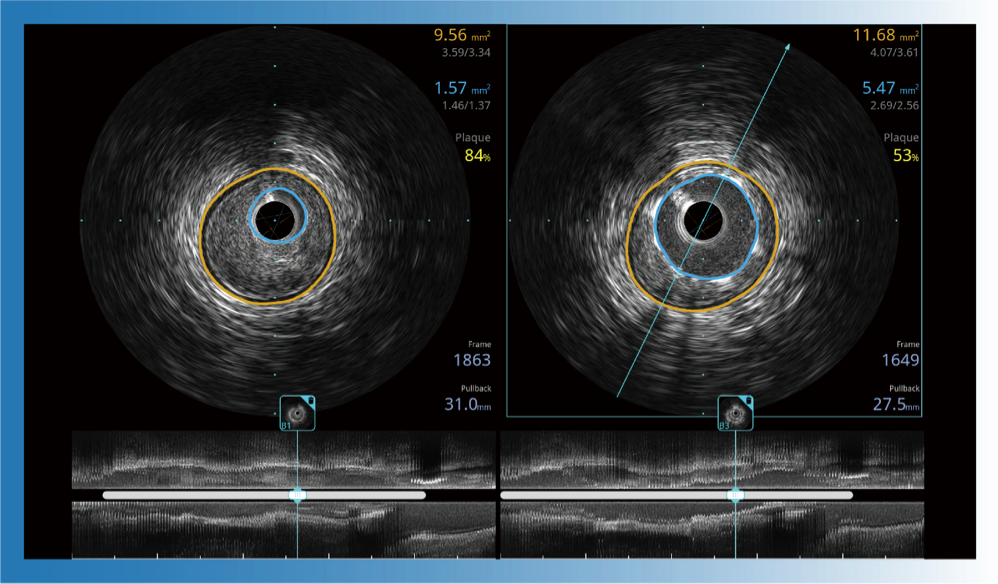

治療前后兩次測量錄像對比

簡化療效評估

一鍵智能描跡,自動測量斑塊負荷、面積狹窄率等指標,準確率高于90%